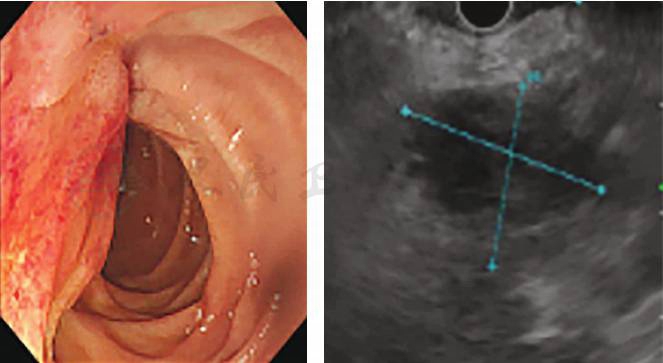

考虑贫血严重,全身情况较差,入院后给予补液扩容改善贫血等支持治疗,血红蛋白纠正至74g/L。第3天:患者排黑便数次,量1 000mL左右,急查血红蛋白53g/L。初步诊断急性消化道出血,首选早期胃镜检查。数字减影血管造影(digital subtraction angiography,DSA)与CTA检查同样具有较好的诊断价值,结合该患者具有十二指肠乳头占位,肿瘤合并出血的可能性较大。因此,首先选择了急诊胃镜检查,发现十二指肠乳头处有隆起占位性病变,局部黏膜粗糙,并有持续少量渗血(图4)。为控制出血,我们继而选择了数字减影血管造影(DSA)栓塞胃十二指肠动脉(gastroduodenal artery,GDA)止血(图5)。DSA术后1周,患者出血停止,血红蛋白逐渐上升至71g/L。

图4 急诊胃镜见乳头占位伴渗血

患者病情趋于稳定,遂决定进一步明确病因及病变部位。根据急诊胃镜检查的发现,患者十二指肠乳头周围存在病变,医师更加针对性地选择了超声内镜+活检检查:壶腹周围低回声灶,范围约2.0cm×1.8cm,胰头癌累及十二指肠可能。胆总管及胰管存在积血可能(图6)。病变黏膜活检结果提示为十二指肠慢性黏膜炎(图7)。为更好地判断病变与周围重要血管的关系及手术可切除性,完善肠系膜上血管计算机断层扫描静脉造影(computed tomographic venography,CTV)检查(图8),见壶腹部占位与肠系膜上动静脉存在间隙,GDA栓塞后周围水肿渗出。

图6 超声内镜提示壶腹周围肿瘤